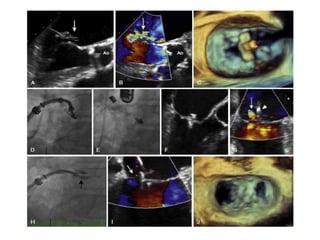

• #7 Mitral valve anatomy. (A) Left ventriculogram in the left anterior oblique projection shows the mitral valve in short axis, with labeled leaflet segments. (B) A schematic diagram of the mitral valve in short axis. (C) A transthoracic echocardiographic image of the mitral valve in the parasternal short-axis projection. A1, A2, and A3, Lateral, central, and medial scallops of the anterior leaflet; P1, P2, and P3, lateral, central, and medial scallops of the posterior leaflet.

• #32 Fig. 52.7 MitraClip repair of posterior leaflet flail. (A) P2 flail (arrow) with (B) anteriorly directed mitral regurgitation (MR) (arrow); (C) 3-D transesophageal echocardiography shows the clip in the left atrium perpendicular to the coaptation line; fluoroscopic projections of the clip (D) open in the left ventricle and (E) closed on the valve; (F) clip grasping the mitral valve (MV); (G) moderate residual MR (arrow) just medial to the clip (arrowhead); (H) second clip (arrow) placed just medial to the first; (I) trivial residual MR (arrow); (J) double-orifice MV after two clips placed. Ao, Aorta.

• #33 MitraClip leaflet coaptation system (Abbott Vascular) creates a bridge between the P2 and A2 segments of the mitral valve similar to the Alfieri stitch operation (A) utilizing a clip delivery system (B) and the MitraClip NT (C). D, Side view, and E, left atrial view, of the clip delivery system as it is advanced through the mitral valve in the open position prior to grasping of the leaflets. F, The final result is illustrated after the clip has been released and the delivery system removed. (Courtesy Abbott Vascular, Inc.)